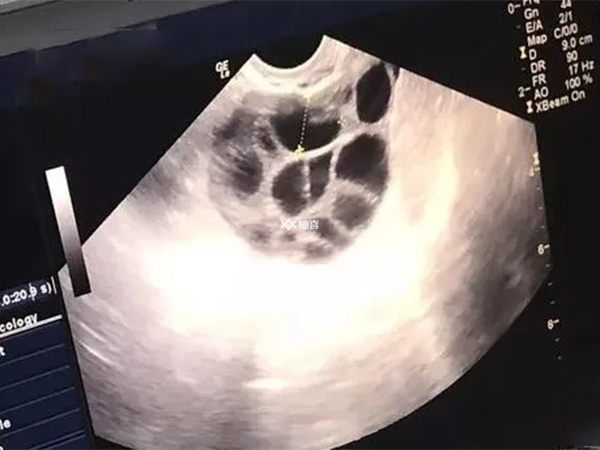

近年来,随着辅助生殖技术的快速发展,试管婴儿已成为许多不孕不育家庭的选择。然而,在试管助孕过程中,有些患者可能会遇到“空卵泡”的情况。所谓空卵,是指在促排卵周期或自然周期中,血清雌二醇( E2)水平及B超下监测卵泡发育良好, 但穿刺取卵时未获得卵母细胞。就像是花生一样,有的花生看起来大而成熟,但是剥开后却是空的,或者花生粒很小。那么这究竟是为什么呢?

在促排卵过程中,虽然有多个卵泡受到药物刺激开始生长,但由于患者体内内分泌紊乱,如高雄激素血症和高胰岛素血症等,会干扰卵泡的正常成熟过程。这可能导致卵泡在形态上看似成熟,但内部卵子却没有真正成熟,从而出现空卵泡。而且卵巢功能不好的人群,卵子从卵泡壁脱落存在困难,更易出现空泡。